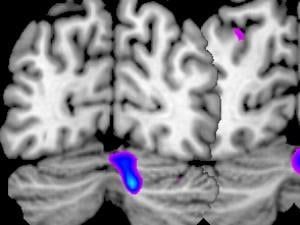

Shared facilities: Cognitive Neuroimaging Centre

cognitive neuroimaging centre

The Cognitive Neuroimaging Centre (CoNiC) houses a 3 Tesla Siemens MAGNETOM Prisma MRI scanner, a magnetoencephalography (MEG) system, and multiple electroencephalography (EEG) systems. Each of these scanners helps researchers examine the structures and functions of the human brain. The Cognitive Neuroimaging Centre is located at the NTU Lee Kong Chian School of Medicine’s Experimental Medicine Building.

The Clinical Brain Lab (CBL) conducts neuropsychological, neuroimaging, and neuromodulation research on brain functions and mental processes that influence learning and behaviour. The lab’s research methods include functional Magnetic Resonance (fMRI) and Transcranial Magnetic Stimulation (TMS). CBL is located at the Division of Psychology within NTU’s School of Humanities and Social Sciences.